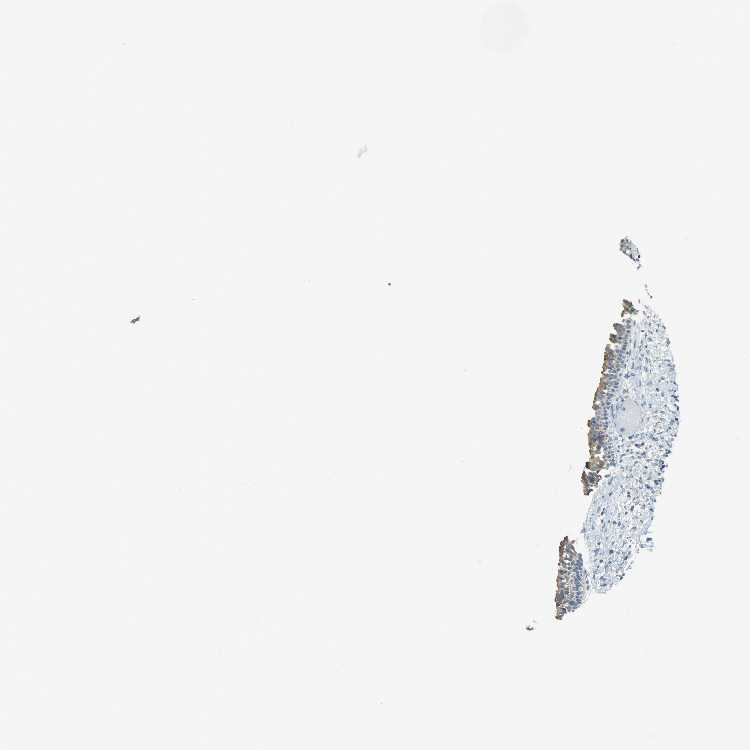

NASOPHARYNX - Antibody stainingi

Antibody staining in the annotated cell types in the current human tissue is reported as not detected, low, medium, or high, based on conventional immunohistochemistry profiling in selected tissues. This score is based on the combination of the staining intensity and fraction of stained cells.

Each image is clickable and will lead to virtual microscopy that enables deeper exploration of all samples and also displays staining intensity scores, fraction scores and subcellular localization as well as patient and tissue information for each sample.

Antibody HPA012820

Respiratory epithelial cells Medium